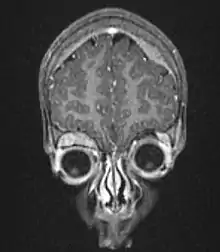

| Microscopic view of a typical neuroblastoma with rosette formation | |

On microscopy, the tumor cells are typically described as small, round and blue, and rosette patterns (Homer Wright pseudorosettes) may be seen. Homer Wright pseudorosettes are tumor cells around the neuropil, not to be confused with a true rosettes, which are tumor cells around an empty lumen.[28] They are also distinct from the pseudorosettes of an ependymoma which consist of tumor cells with glial fibrillary acidic protein (GFAP)–positive processes tapering off toward a blood vessel (thus a combination of the two).[29] A variety of immunohistochemical stains are used by pathologists to distinguish neuroblastomas from histological mimics, such as rhabdomyosarcoma, Ewing's sarcoma, lymphoma and Wilms' tumor.[30]